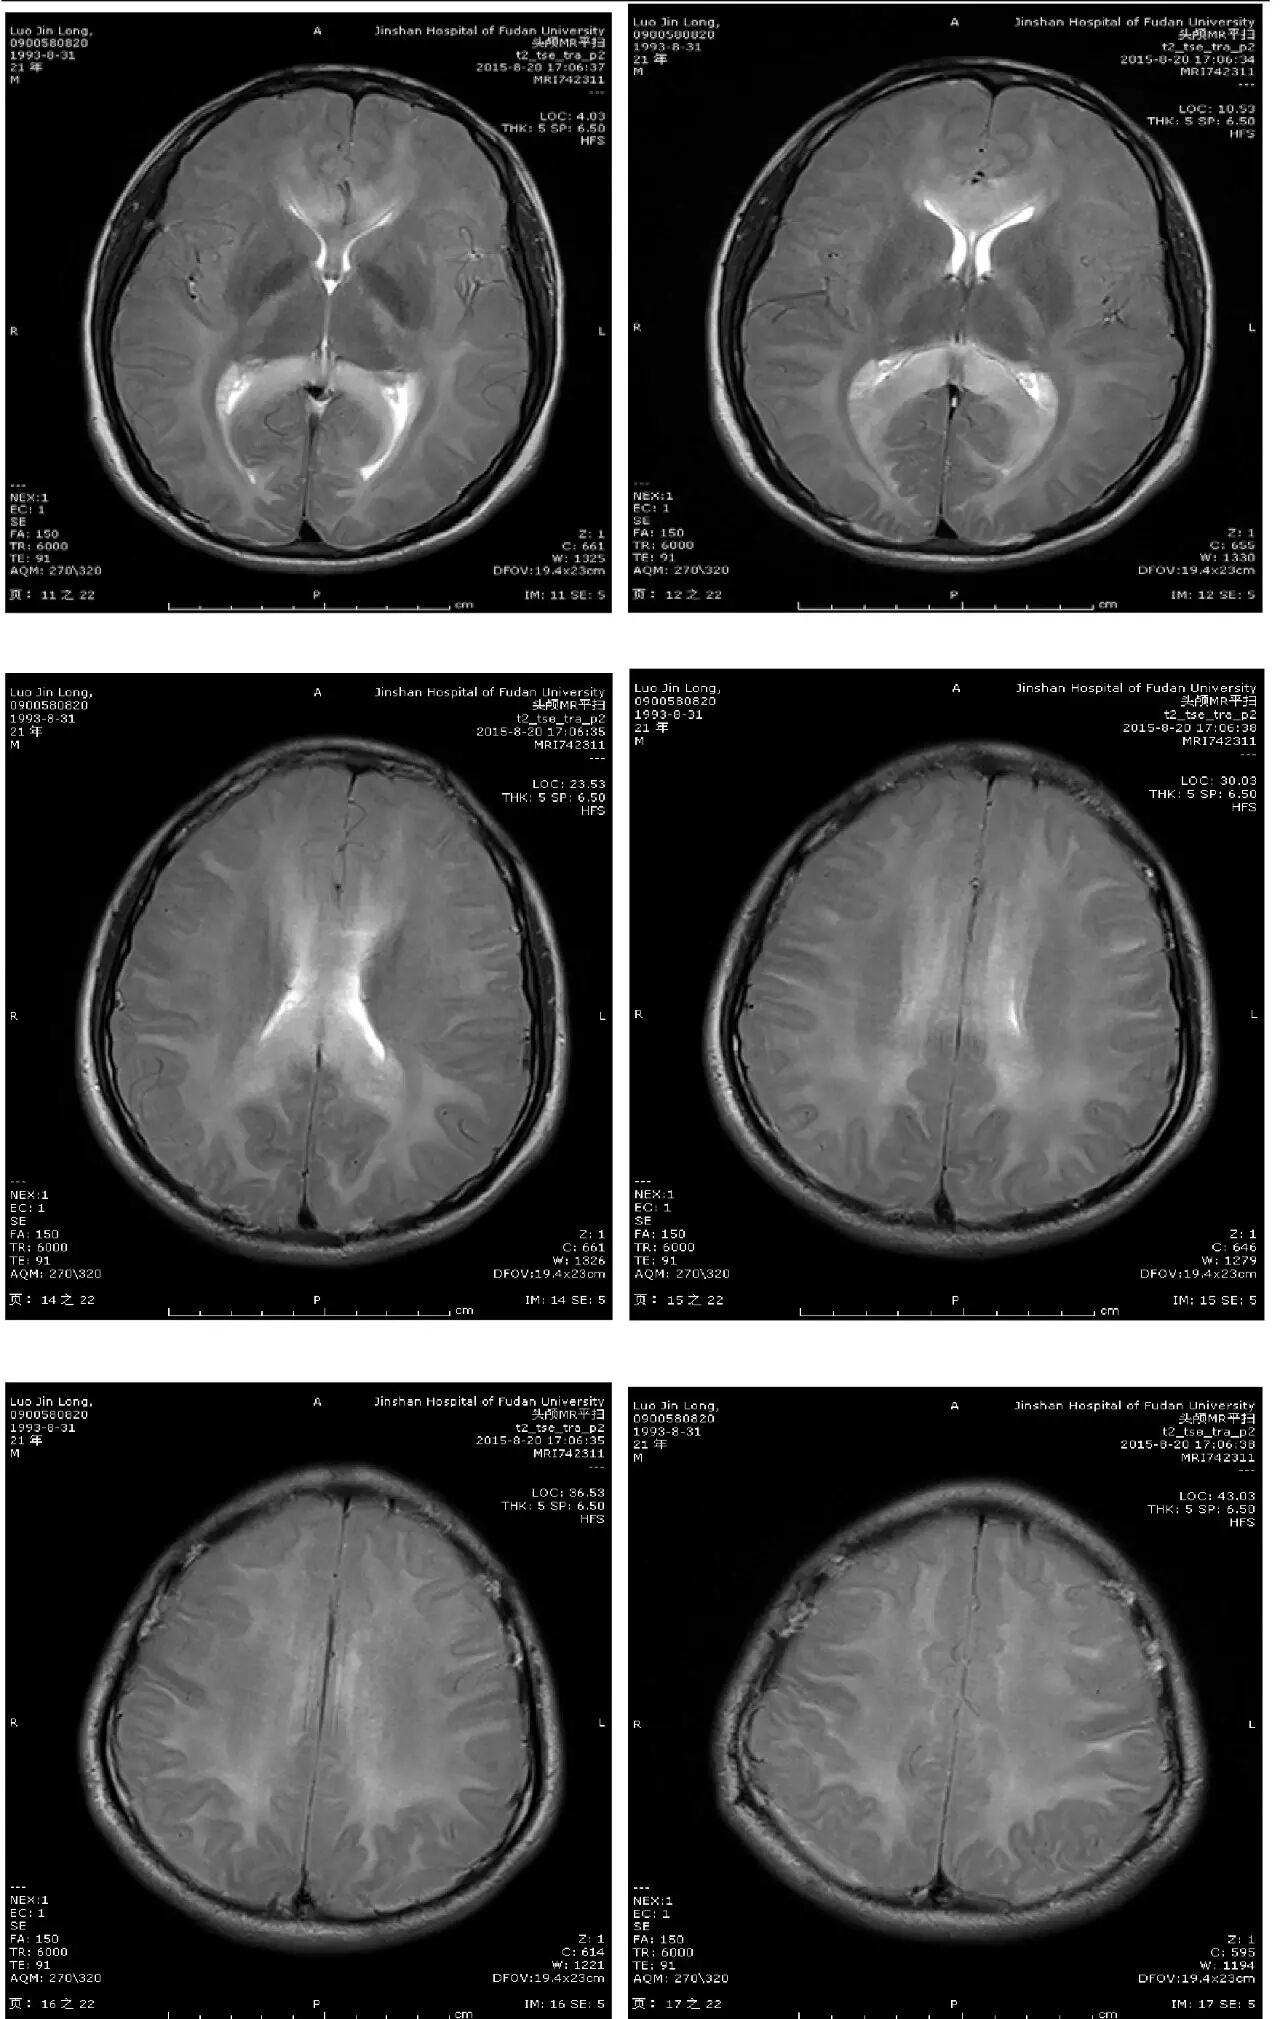

主诉:头痛、反应迟钝、口齿不清4天

现病史:头中线部位钝痛,反应迟钝,口齿不清,无发热,无恶心、呕吐,无饮水呛咳,四肢乏力。无麻木不适。2天后出现视物模糊。外院头颅CT:两侧大脑半球低密度灶。

入院体检:T:36.5℃,血压,100/60mmHg。神志清楚,口齿不清,对答切题。双侧瞳孔等大等圆,直径0.25cm,对光反射灵敏,无眼震,口唇无紫绀,双侧鼻唇沟对称,伸舌不偏。抬头有力。颈软,无抵抗,颈动脉听诊未及杂音。双肺呼吸音清,未及明显干湿性啰音。心界临界,心率56次/分,律齐。䏡双下肢不肿。四肢肌力V级,肌张力不高,病理征未引出。双侧肢体针刺觉、振动觉对称存在。双侧轮替动作、指鼻试验及跟膝胫试验阴性。